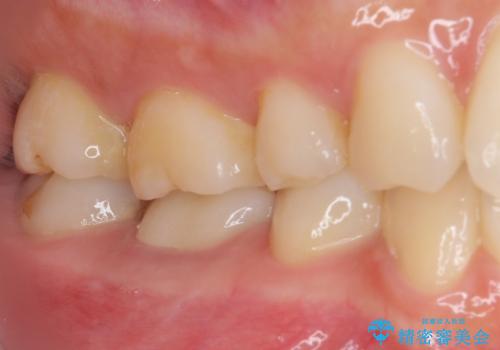

前医での根管治療の度に感じていた痛みの原因は分かりませんでしたが、元々違和感すらなかった歯であったので、速やかに根管治療を行った後に、ジルコニアクラウンを装着しました。

咬み合わせが強く、歯の高さが非常に低かったため、審美性には劣るものの、高強度であるフルジルコニアクラウンを採用しました。